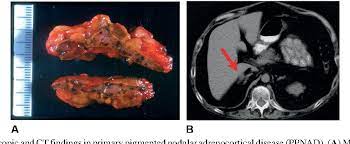

Ppnad is defined as primary pigmented nodular adrenocortical disease somewhat frequently. Ppnad is more frequent in females, especially after puberty. Define the genetic basis for ppnad and/or the carney complex. The liddle test is a test that doctors can use to help determine whether persons with the cushing syndrome have it because primary pigmented nodular adrenocortical disease (ppnad). Looking for the definition of ppnad? Cnc is a rare syndrome that involves the formation of abnormal tumours that cause endocrine hyperactivity. This page is about the various possible meanings of the acronym, abbreviation, shorthand or slang term: Biochemically, ppnad is characterized by elevated levels of plasma and urinary cortisol that are not suppressed by high doses of dexamethasone (8mg/d for 2 days). Identify carriers of the disease. Ppnad is an acronym for primary pigmented nodular adrenocortical disease. Ppnad arises due to the enlargement of the cortex of the adrenal glands, resulting in cushing's syndrome that is independent of the pituitary hormone acth.1. Primary pigmented nodular adrenocortical disease (ppnad) was first coined in 1984 by carney et al. Ponad in wielki słownik języka polskiego, instytut języka polskiego pan.

Cnc is a rare syndrome that involves the formation of abnormal tumours that cause endocrine hyperactivity. Ponad in polish dictionaries at pwn. Ponad in wielki słownik języka polskiego, instytut języka polskiego pan. Primary pigmented nodular adrenocortical disease (ppnad) was first coined in 1984 by carney et al. Ppnad is responsible for less than 2% of cases.